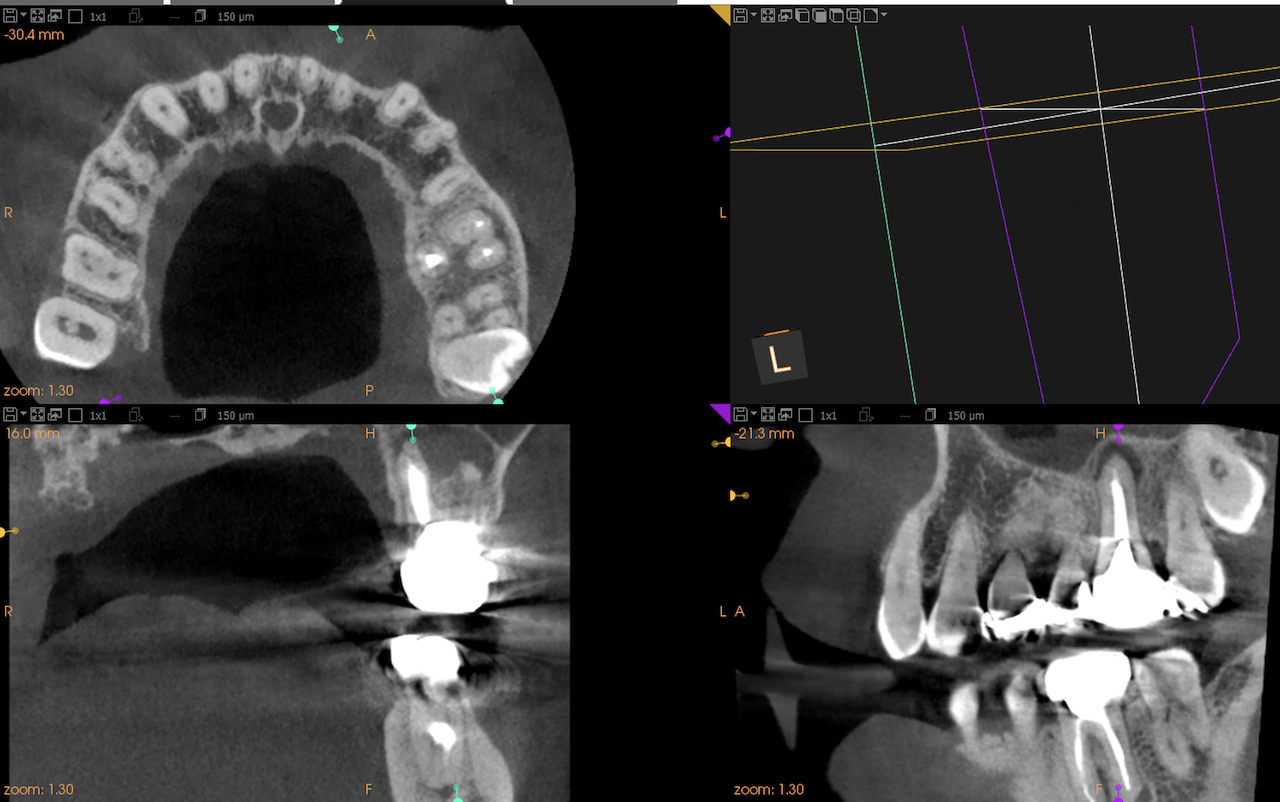

#14 Intentional Replantation 1yr recall(2025.6.6)

MB

DB

P

上顎洞炎は治癒し、Pの歯槽骨はかなり回復したがMB,DBは口腔内に歯根が出てしまっている。

つまりここがエンドポイントになるだろう。